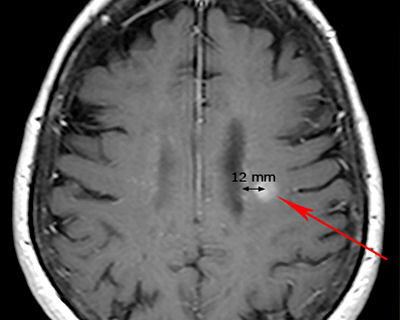

Periventricular

MS lesion